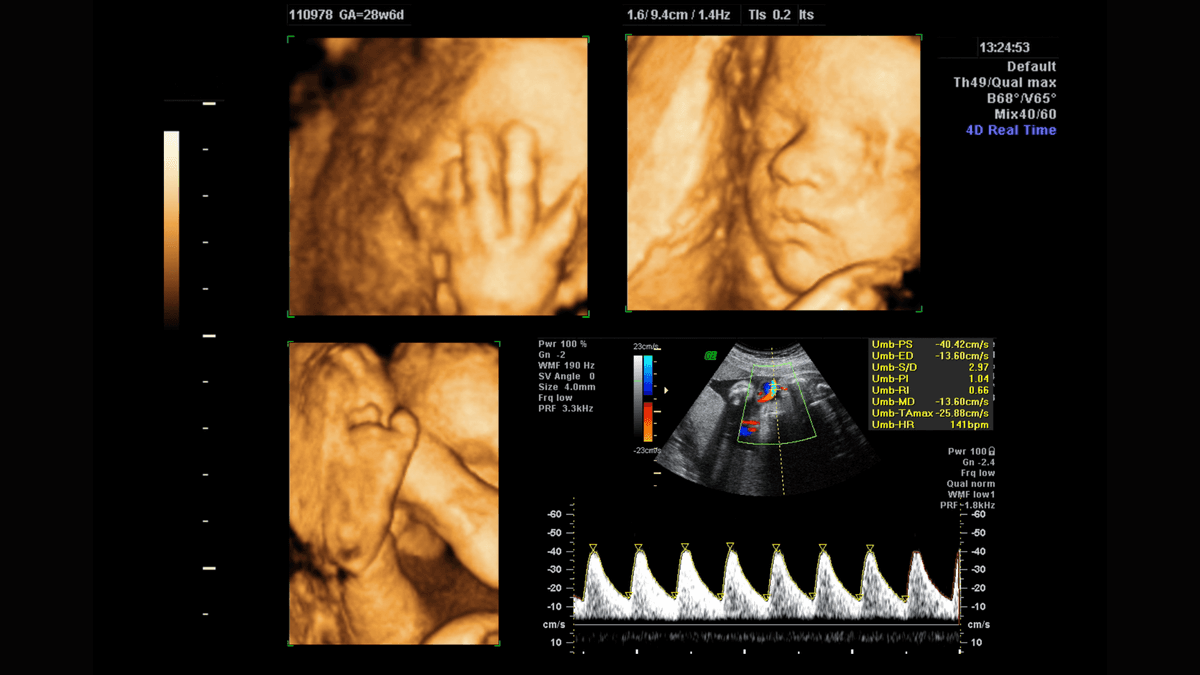

Pregnancy is a sensitive and critical phase where every medical decision is taken with extra caution to protect both the mother and the developing baby.

The baby undergoes rapid changes, including increased fat accumulation, strengthening of muscles, and continued development of vital organs.

Medically referred to as an echogenic intracardiac focus (EIF), appears as a small, bright area within one of the baby’s heart chambers.

Many expectant parents eagerly listen to the rhythmic beat of their baby’s heart during prenatal checkups.

One of the key elements that contribute to a healthy and safe pregnancy is timely and accurate medical imaging.

Ultrasound imaging has long been a staple of prenatal care. It uses high-frequency sound waves to produce images of the baby inside the womb.

This non-invasive imaging technique not only provides a first glimpse of the baby but also plays a pivotal role.